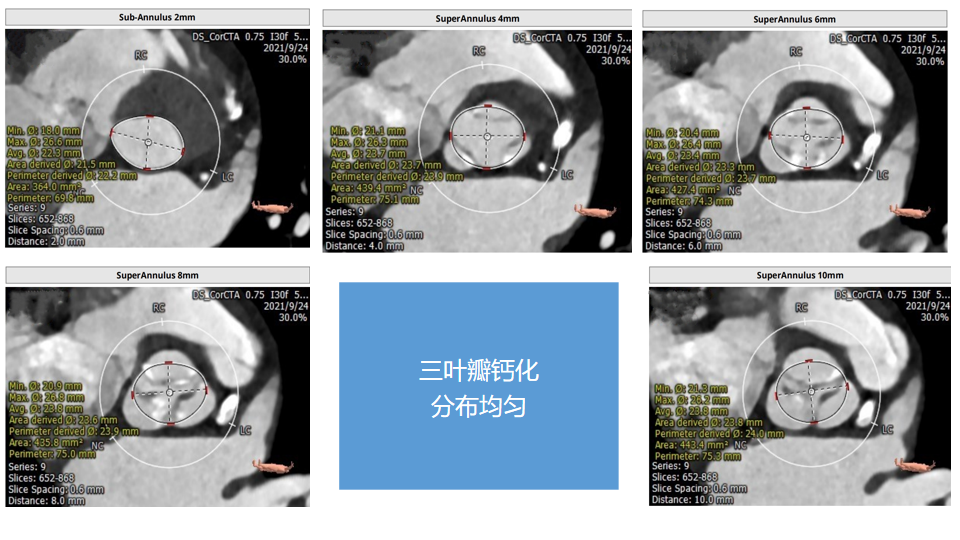

主动脉瓣CT评估:三叶瓣,双冠脉开口水平可,钙化分布较均匀。双侧髂股动脉内径可。瓣环长短径分别为17.9*25.1mm,周长为68.8mm,面积为358.1mm²。

瓣上多平面测量: